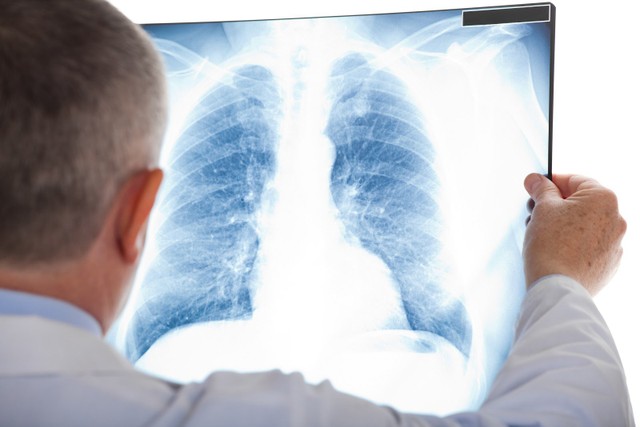

Tràn mủ màng phổi xảy ra khi dịch mủ tích tụ trong khoang màng phổi, gây ra những triệu chứng nguy hiểm và đe dọa đến tính mạng nếu không được điều trị kịp thời. Tình trạng này không chỉ gây ra đau đớn và khó thở cho bệnh nhân mà còn có thể dẫn đến nhiều biến chứng nguy hiểm như suy hô hấp, nhiễm trùng lan rộng và áp xe phổi. Trong bài viết dưới đây, bạn sẽ được tìm hiểu rõ hơn về tình trạng y tế nghiêm trọng này.